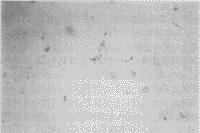

细胞培养3~5天后,细胞贴壁,体积小,圆形,分散存在,部分细胞有轴突伸展(照片1)。微波辐照后,Ⅰ组细胞发生聚集,仍可见轴突,细胞边界清楚(照片2);Ⅱ组细胞聚集成团,少数细胞散在,轴突消失,边缘较模糊(照片3),偶见“环状”细胞出现(照片4);Ⅲ组细胞与Ⅱ组相似,散在细胞较多;Ⅳ组细胞多数边界模糊,部分细胞漂浮,可见细胞碎片(照片5)。辐照后细胞继续培养48小时后,Ⅰ组细胞大部分散在,少量聚集(照片6),Ⅱ组细胞仍聚集成团,但细胞亮,边缘清楚,Ⅲ组变化不明显,Ⅳ组细胞减少,杂质多。

1 正常RGC形态(×250)

2 10mW/cm2(30min)辐照后细胞形态(×250)

3 10mW/cm2(60min)辐照后细胞形态(×250)

4 10mW/cm2(60min)辐照后凋亡样细胞(×400)

5 30mW/cm2(60min)辐照后细胞破坏较重(×250)

6 辐照后再培养48h的细胞形态(×250)

附图 微波辐照及再培养对细胞形态的影响